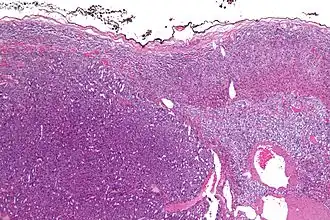

Адренокортикальный рак (англ. adrenocortical carcinoma) — редкая злокачественная опухоль, исходящая из коркового слоя надпочечника[1]. Встречается с частотой 2-4 случая на 2 миллиона населения[2].